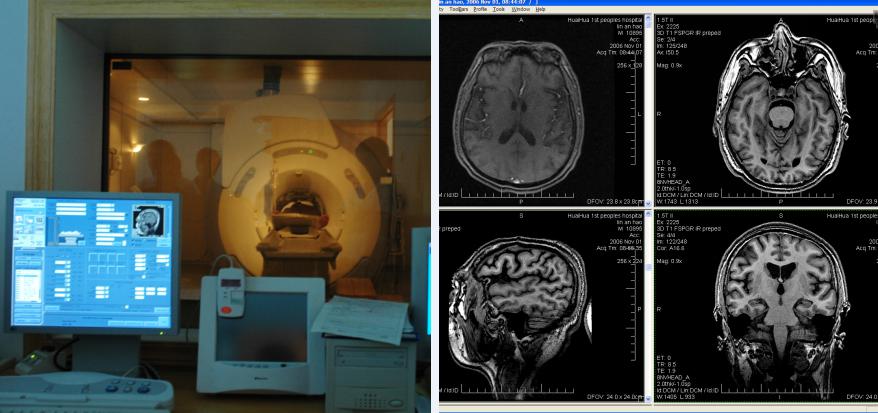

20世紀(jì)70年代,計(jì)算機(jī)輔助的X線斷層掃描(CT)的問世及80年代初磁共振成像技術(shù)(MRI)的出現(xiàn)使顱內(nèi)病變定位診斷發(fā)生了重大變化。這種腦神經(jīng)解剖圖像技術(shù)檢查時(shí)患者既無痛苦,又可以使顱內(nèi)的解剖結(jié)構(gòu)與其病變的情況以可視辨別的圖像,清晰的展示在人們眼前。而立體定向技術(shù)很快與CT、MRI掃描配準(zhǔn)成一體的進(jìn)步,從而使CT、MRI引導(dǎo)的腦立體定向下微創(chuàng)神經(jīng)術(shù)在功能神經(jīng)外科得到廣泛應(yīng)用,該手術(shù)極大程度上減少了手術(shù)的流程,同時(shí)采用的微創(chuàng)手術(shù)傷口僅為1-3cm的小切口,減少了患者手術(shù)遭受的痛苦,并發(fā)癥少,取得了良好的效果。

在21世紀(jì)里,科學(xué)的發(fā)展異常迅猛,在原有的CT、MRI引導(dǎo)的腦立體定向下微創(chuàng)神經(jīng)調(diào)控術(shù)之上,結(jié)合了彌散張量成像(DTI)技術(shù)的第五代腦立體定向下微創(chuàng)神經(jīng)調(diào)控術(shù)問世。相較之前最¨大的提升之處在于,第五代腦立體定向下微創(chuàng)神經(jīng)調(diào)控術(shù)中的DTI技術(shù)可以精¨確的顯示腦功能神經(jīng)傳導(dǎo)束,手術(shù)時(shí)可以更有效的避開腦功能神經(jīng),使手術(shù)更加安全,確?;颊咝g(shù)后不會(huì)出現(xiàn)其他問題。其次,DTI、MRI與CT的融合定位已經(jīng)邁入數(shù)字定位時(shí)代。數(shù)字定位是目前最精準(zhǔn)的定位方式,其定位誤差僅在±0.01毫米。